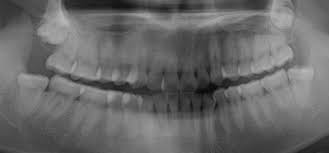

Der eine Nerv ist der Nervus alveolaris inferior der unterste Ast des Trigeminus-Nervs. Hatte ich noch nie eine Spritze im Mund. Weisheitszahn und zyste nerv nah - risiko.

Häufig verläuft ein Nerv entweder durch die Wurzeln oder am Zahn entlang. Und bei nicht wenigen war es der fall dass der eingriff nah am nerv vorgenommen wurde das risiko also da war. Bevor ich meinen körper über jahre mit schmerzmitteln schädige und schmerzen leide würde ich mich diesem eingriff unterziehen.

Sie liegen sehr nah am Nerv weshalb der Arzt nur zwei auf Einmal zieht. Bei der lokalen Narkose besteht das Risiko vor allem dadurch dass durch die Nadel ein Nerv beschädigt wird.